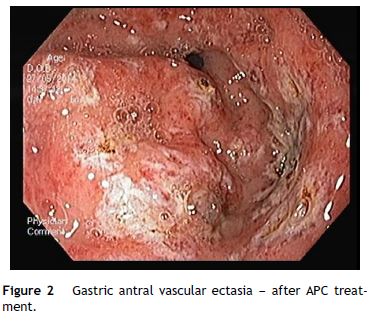

An OGD was performed and revealed multiple erythematous spots in the antrum compatible with GAVE, diffuse type (Fig. 1), and mild portal hypertensive gastropathy, without active bleeding. There was no evidence of esophageal or gastric varices. GAVE was treated with APC without complications (Fig. 2). A colonoscopy with ileoscopy was also performed, but it was negative for blood or hemorrhagic lesions. Her hemoglobin levels remained stable and the patient was discharged and started on propranolol (for portal hypertensive gastropathy), with a target of 55 beats per minute, 40 mg of pantoprazole every 24 h and performed iron intravenous supplementation in ambulatory.

During the following 4 months, the patient had 3 new episodes of severe symptomatic anemia requiring transfusion. During these episodes she underwent OGD that revealed persistence of GAVE and APC treatments were performed.